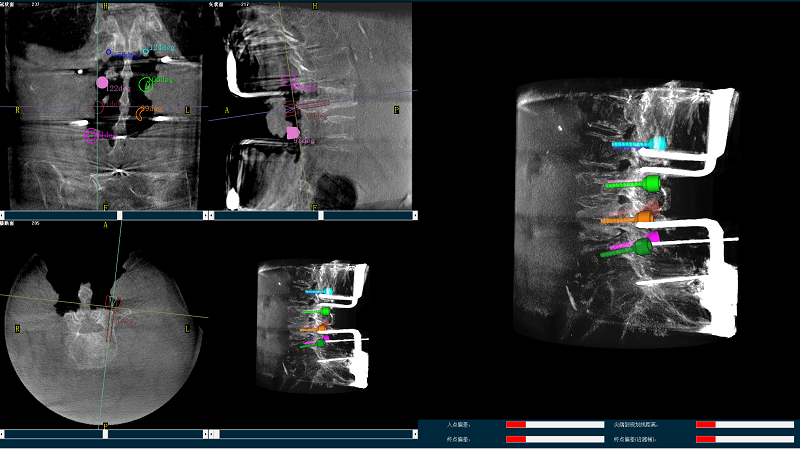

機(jī)器人輔助腰椎后路側(cè)彎矯形手術(shù)規(guī)劃圖像

手術(shù)規(guī)劃圖像

(4)在骨科機(jī)器人導(dǎo)航系統(tǒng)輔助下,一次性準(zhǔn)確植入8枚椎弓根螺釘。